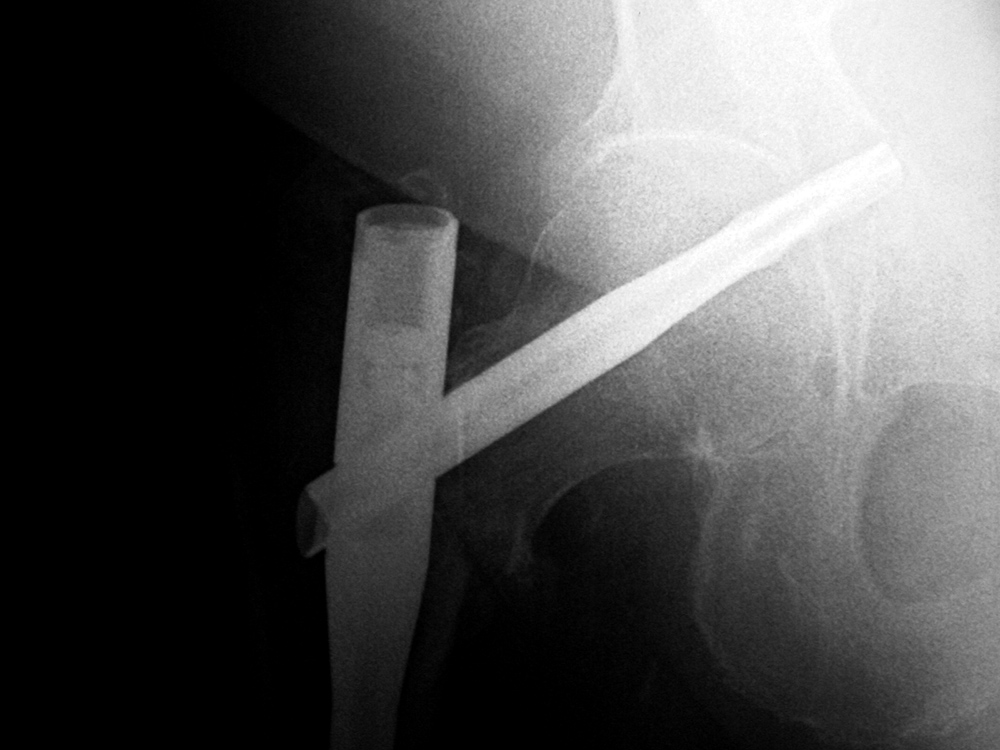

Intraoperative fixation of an intertrochanteric fracture demonstrates a cephalomedullary device with the tip of the cephalic screw positioned too short and very inferior in the neck (very large tip-apex distance). |

Subsequent fracture fixation failure observed as the head and neck segment of the femur flexed 90 degrees with cut-out of the screw approaching the hip joint. |